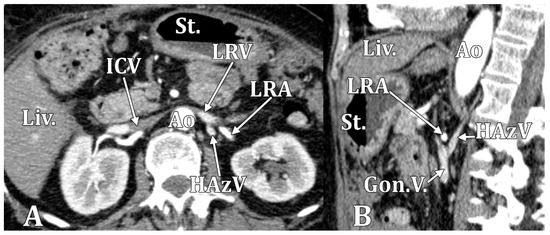

| ALV | ascending lumbar vein |

| HAzV | hemiazygos vein |

| LRV | left renal vein |

| RHC | reno-hemiazygos connection |

| RLRV | retroaortic left renal vein |

| LRV | LRV/RP | RLRV | CLRV | |

|---|---|---|---|---|

| Type 1 (11 cases) | 7 (63.64%) | 1 (9.09%) | 1 (9.09%) | 2 (18.18%) |

| Type 2 (3 cases) | 2 (66.67%) | – | – | 1 (33.33%) |